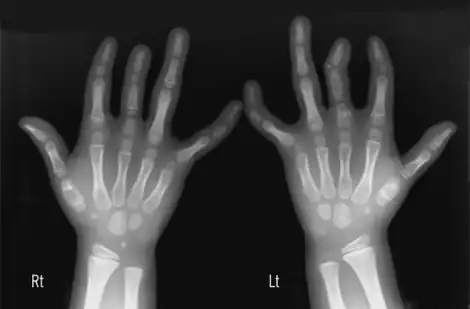

Brachydactyly

Brachydactyly (Greek βραχύς = "short" plus δάκτυλος = "finger"), is a medical term which literally means "short finger". The shortness is relative to the length of other long bones and other parts of the body. Brachydactyly is an inherited, usually dominant trait. It most often occurs as an isolated dysmelia, but can also occur with other anomalies as part of many congenital syndromes. Brachydactyly can also be a signal that one will be at risk for heart problems as they age.